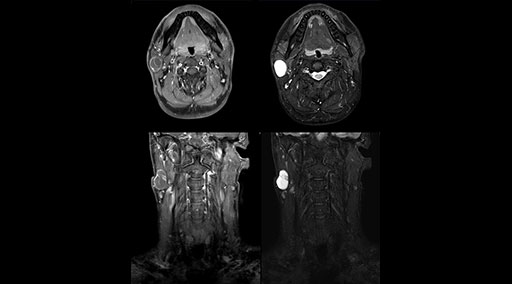

“Our DMG Lisle location includes a cancer center, so soft tissue neck scans, brachial plexus scans, and prostate scans are common. For these exams, mDIXON TSE provides excellent images with and without fat suppression all while helping us reduce repeats and work more efficiently,” Mr. Duffy says.

“mDIXON TSE raises our diagnostic confidence with its homogeneous

fat suppression. Neck exams and rheumatology patients are two examples where mDIXON TSE is especially useful,” Dr. Kaakaji says. “For us it’s also an efficiency boost in exams where we need pre and post T1-weighted images with great fat suppression.”